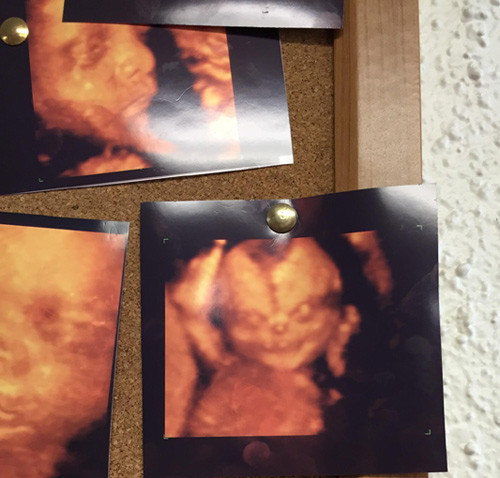

Tiến sĩ Nadja Reissland nghiên cứu những hình ảnh siêu âm 4D của hàng nghìn hành động rất nhỏ của thai nhi, đặc biệt ở những bà mẹ hút thuốc lá. Trong khi những bà mẹ không hút thuốc thường thai nhi không có những biểu hiện như trên.